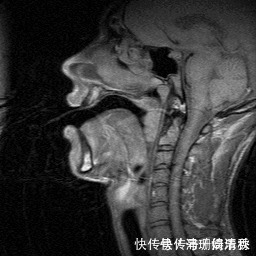

02宝宝说话晚的原因宝宝说话晚,大部分是由以下原因造成的。辅食过于精细,咀嚼功能练习不够大人总是担心孩子吃的食物太硬,不利于消化和吸收,就会把辅食做得很精细。但这样宝宝的咀嚼功能就得不到很好的锻炼,在一定程度上会影响到口腔肌肉的发育,进而影响到语言发育,出现说话晚、发音不准的问题。【 家长|宝宝很聪明,就是说话晚、说不清?讲真,“元凶”可能是家长】

(说话时口腔肌肉的运动)家庭环境中缺乏沟通交流说实话,除了胖这种技能是与生俱来,且完全不需要学习以外,其他技能都要学习。同理,想让孩子说话,多沟通是必不可少的。别管孩子能不能听懂,会不会回应,你都得多和他说话,这样才能保证有足够的语言输入。只要他在努力发出不同音强、音调、音质的声音,那就说明孩子准备说话,你回应得越多,越把它们当成真正的讲话,越能激发孩子交流的欲望。大人“太善解人意”现在几乎家家都有一个“高级翻译家”。孩子不需要说话,确认过眼神,就知道你想要什么。在我家,姥姥就是个“顶配翻译机”,只要娃一伸手、哼哼两声,我妈立马就能get到娃的需求,整个过程持续时间也就2秒钟......这就直接导致糖糖,越来越懒,越来越懒,最后直接懒得说了......反正你们都懂我的意思......屏幕时间过长我老妈经常说的一句话就是:哎呀,你看宝宝多聪明啊,这么小,玩手机玩得可溜了,比我都厉害!眼神中透漏着无以言表的“骄傲”!可实际上,电子产品、电视对孩子而言,是单向输入,孩子不能产生双向互动,屏幕时间太长对语言发育也是有害无利。此外,若孩子一直处于环境变迁,家人语言输入不一致的情况中,也多多少少会影响到语言发育。03做互动型父母,促进孩子语言发育想要改善孩子说话晚、说话不清的状况,最重要的是咱大人先改变观念。而最重要的一点,就是要学会做互动型家长,在玩乐中潜移默化地影响孩子,促进孩子语言能力的发育。具体怎么做,赶紧跟着糖妈一起来康康叭~1 成为孩子最好的玩伴孩子最好的玩伴,不是多智能的电子产品,也不是有多少精致的玩具,而是你!只有跟孩子充分地互动,才能有效地帮助孩子发展语言和沟通技能。家长一定要get到下面这些tips:同看——玩孩子想玩的在陪玩的过程中,要以孩子的喜好为标准,他喜欢玩汽车咱就玩汽车,他喜欢布娃娃那就玩布娃娃......同说——说孩子想说的孩子词汇的习得,都与周边感兴趣的人、事、物相关。例如,孩子指着地上的小蚂蚁,特别兴奋地喊“啊啊啊”,这个时候咱就要说“小蚂蚁”,然后给孩子一段反应时间,给他们重复说的机会。同玩——用孩子的方式玩大人要时时“戏精附身”,陪玩时把自己的心智放到2、3岁。观察孩子的行为,模仿孩子的玩法。例如躲猫猫、过家家等都是很棒的互动游戏。